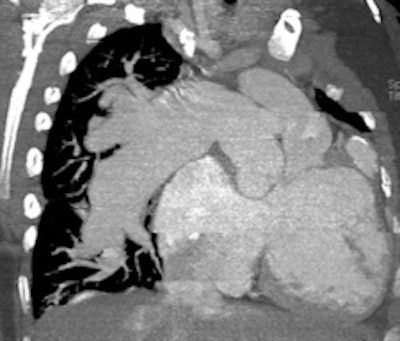

Retrospective ECG-gated study on a 5 year old with severe pulmonary hypertension. The CT images show dilated pulmonary arteries (top left). There is right atrial and ventricular dilatation with hypertrophy and bowing of the interventricular septum into the left ventricle (arrow, top right). There is abnormal arborization and angulation of the peripheral pulmonary arteries (top right, bottom), with multiple peripheral centrilobular nodules with perilesional ground-glass attenuation. Features are in keeping with pulmonary capillary hemangiomatosis.